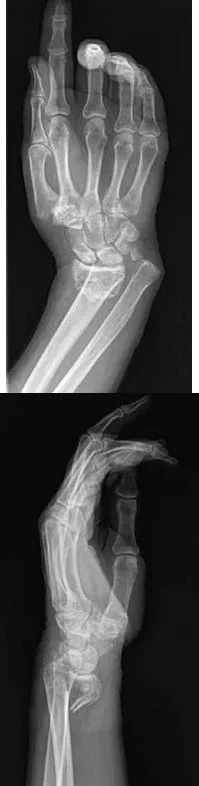

A 64-year-old woman sustains the wrist injury shown in the radiographs. The injury is a volar displaced intra-articular distal radius fracture. When utilizing a volar buttress plate for this specific fracture pattern, what is the primary biomechanical function of the plate?

Explanation

Correct Answer: C

The radiographs show a volar Barton's fracture (volar displaced intra-articular fracture of the distal radius). The primary deforming forces are axial loading and volar shear, which cause the carpus to subluxate volarly with the fracture fragment. A volar buttress plate is applied to physically block (buttress) this volar displacement, neutralizing the axial and shearing forces.

A 64-year-old woman sustains the wrist injury shown in the radiographs after a fall on an outstretched hand. The fracture pattern involves a volar displaced intra-articular fragment. What is the primary biomechanical rationale for utilizing a volar buttress plate in the surgical management of this specific injury?

Correct Answer: It neutralizes axial loading forces on the fractured volar fragment.

The radiographs demonstrate a volar Barton's fracture, which is a volar displaced intra-articular fracture-dislocation of the distal radius. The volar carpal ligaments remain attached to the volar fragment, pulling the carpus volarly. A volar buttress plate is biomechanically ideal for this injury because it acts as an anti-glide plate, neutralizing the axial loading and shear forces that drive the fragment proximally and volarly. A dorsal plate would not provide this buttress effect and would make maintaining the reduction difficult.

A 64-year-old woman sustains a wrist injury after a fall. Radiographs demonstrate a volar displaced, intra-articular distal radius fracture-dislocation. Which of the following surgical approaches and fixation methods is most appropriate to neutralize the axial loading forces on the fractured fragment?

Correct Answer: B

The radiographs show a volar Barton's fracture (volar displaced intra-articular distal radius fracture-dislocation). The most biomechanically sound treatment is an open reduction through a volar approach and stabilization with a volar buttress plate. The buttress plate effectively neutralizes the axial loading and shear forces that drive the volar fragment proximally. A dorsal plate cannot provide this buttress effect for a volar shear fracture.